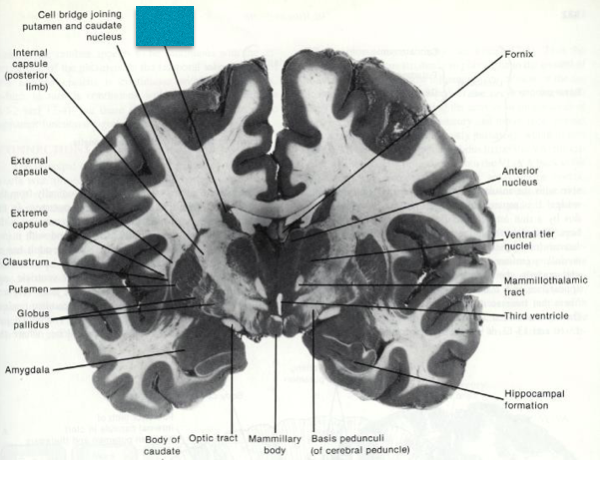

Fill in the blanks.

Fill in the blank.

Fill in the blank

Fill in the blanks